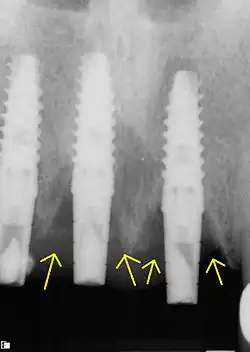

La péri-implantite est la perte progressive de l'os péri-implantaire à la suite d'une réaction inflammatoire[1].

Le risque de péri-implantite est accru lors de la mise en place d'un implant dentaire. La réaction inflammatoire pouvant survenir à la suite du déséquilibre de l'environnement intra-oral induit cette perte osseuse. Il s'agit de la principale source de complications à moyen et long terme des implants dentaires[2]. Selon l'étude Roos-Jansåcker ayant suivi un échantillon de patients, une péri-implantite apparaît dans 16 % des cas de mucosité chez ces derniers (48 % des patients) après 9 à 14 années d'implantation[2],[3].